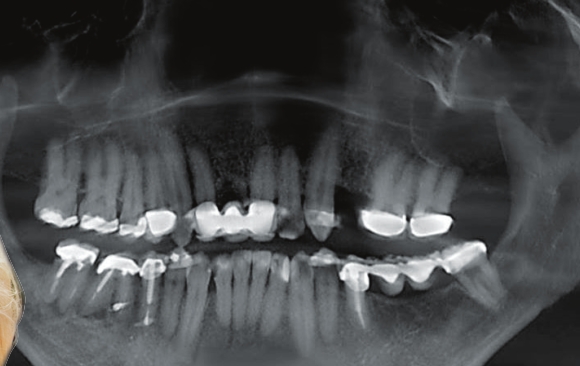

Step 1:

A 3D scan is taken WITHOUT uncomfortable sensors in your mouth. Note the missing tooth in the upper left (your right). This image is a two dimensional rendering of the 3D source image.